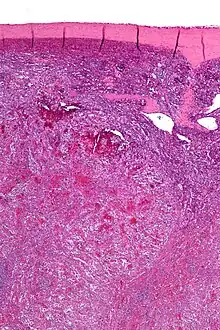

| Low magnification micrograph of a littoral cell angioma. H&E stain. | |

Littoral cell angioma, abbreviated LCA, and formally known as littoral cell angioma of the spleen, is a benign tumour of the spleen that arises from the cells that line the red pulp.[1]

Littoral cell angiomas show in CT scans. They are diagnosed by pathologists by taking a sample of the tumour via Fine Needle Aspiration or Core Needle Aspiration or from a splenectomy. Histologically, they have anastoming small vascular channels and cystic spaces with papillary projections.[2]

Very low mag.